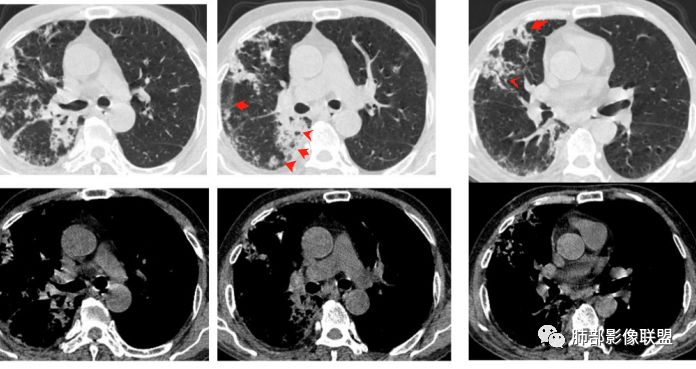

2.双肺多发病灶,主要集中在右肺,斑片影、结节影,条索影,支扩等等,右肺病灶胸膜下居多,密度偏高不均,偶见钙化。

3.右肺巨大空洞影。值得注意的是:

1)空洞内坏死相对彻底(未见絮状物或丝状物等)。

2)空洞壁密实,内外壁都清楚,这是慢性病灶特征之一。

3)内壁不规则,多呈不规则山脊样突入,这些“脊”等同于空洞壁的密实。尽管洞腔内蜿蜒不规则,但并未形成洞壁的膨隆样结节影,换句话说,外壁看不出分叶!

这种空洞更多见于结核!

4)空洞病灶内显示液平。提示伴有细菌感染等。

5)肺门纵隔未见肿大淋巴结。